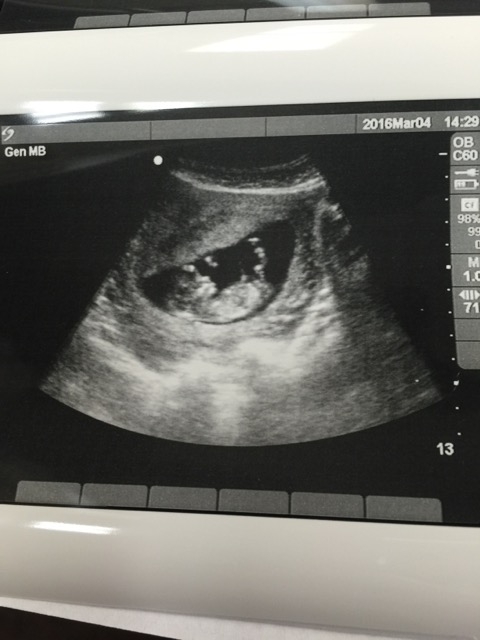

12 weeks and 2 days. HR 161